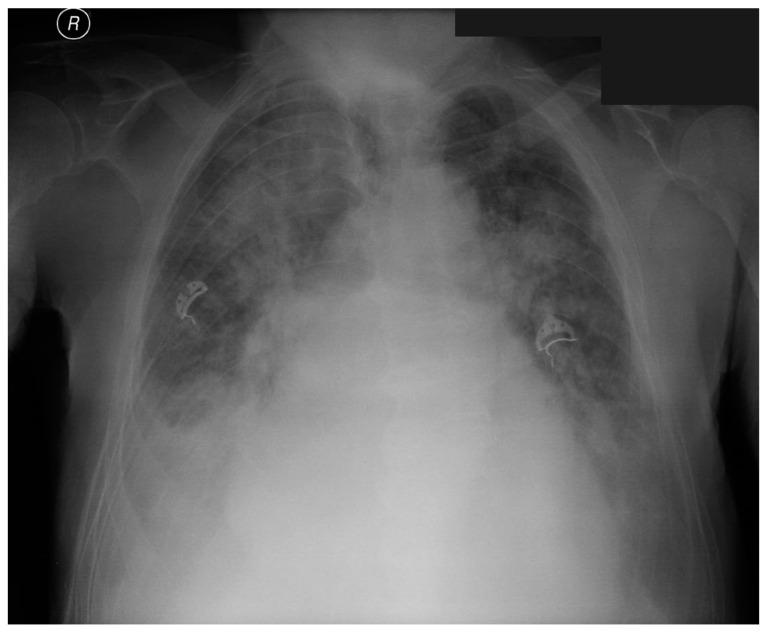

Transcatheter aortic valve implantation (TAVI) is currently becoming the method of choice in high-risk patients with severe aortic valve stenosis. Post-TAVI complications are more common owing to the increasing use of the method. The majority of TAVI complications derive from concomitant aortic stenosis with moderate/severe aortic insufficiency, paravalvular leak, and atrioventricular block. The contemporary TAVI qualification process includes a thorough echocardiography and angio-CT of the aorta, which is crucial in assessing valve measurements, determining the position of the coronary arteries branching from the aorta, and choosing the optimal valve size. We present the case report of an 81-year-old patient admitted to our hospital because of exacerbation of the clinical condition and development of pulmonary edema a few days after TAVI. Despite the reduction of the initial leak, an echocardiographic examination revealed the remaining severe paravalvular aortic leakage. We performed open-heart cardio-thoracic surgery, explanted the TAVI valve, and implanted the biological prosthesis (Edwards Perimount Magna size 25). Introduction of new interventional treatment approaches and the availability of imaging tools have substantially reduced the incidence of significant paravalvular leak and offered a better prognosis for patients undergoing TAVI.

经导管主动脉瓣植入术(TAVI)目前正成为重度主动脉瓣狭窄高危患者的首选治疗方法。由于该方法使用的增加,TAVI术后并发症更为常见。大多数TAVI并发症源于合并中度/重度主动脉瓣关闭不全的主动脉狭窄、瓣周漏和房室传导阻滞。当代TAVI的评估过程包括全面的超声心动图检查和主动脉血管造影CT,这对于评估瓣膜尺寸、确定从主动脉分支的冠状动脉位置以及选择最佳瓣膜大小至关重要。我们报告了一例81岁患者,因TAVI术后几天临床症状加重和肺水肿发展而入院。尽管初始漏血减少,但超声心动图检查显示仍存在严重的瓣周主动脉瓣反流。我们进行了心脏直视胸外科手术,取出TAVI瓣膜,并植入生物假体(爱德华兹Perimount Magna尺寸25)。新介入治疗方法的引入和成像工具的应用显著降低了严重瓣周漏的发生率,并为接受TAVI的患者提供了更好的预后。